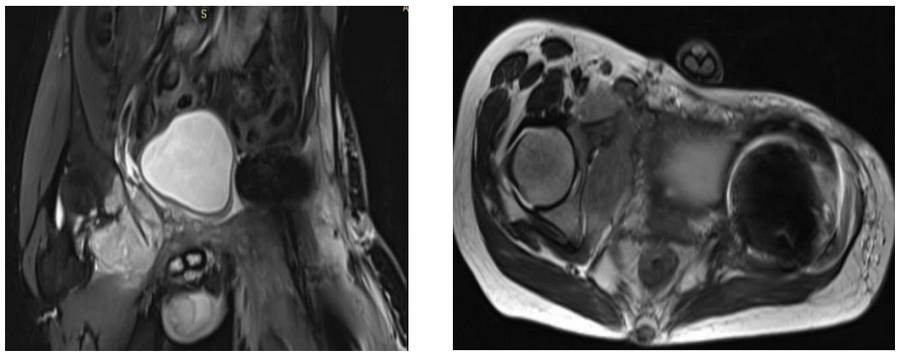

Preoperative: MRI shows tumor tissue extending into the soft tissue of the right acetabulum and pubic arm, causing bone damage.

During the operation: The clinical and radiological images of the removed tumor tissue are shown.